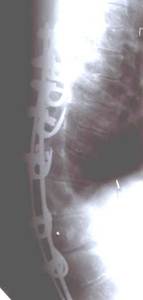

Динамический корректор. Результат на 2-е сутки после операции

В дальнейшем А.А. Гайдуков разработал и создал эндокорректор с деротационными скобами с фиксацией в блоках креплений на нескольких уровнях. Данный эндокорректор позволил эффективно на 60-100% корригировать деформацию при сколиозе III-IV степени. Но тяжелая многочасовая операция, травматичность вмешательства, проволочная фиксация и нередкие неврологические осложнения ограничивали применение данной методики.

Результат коррекции сколиотической деформации эндокорректором с деротационными скобами